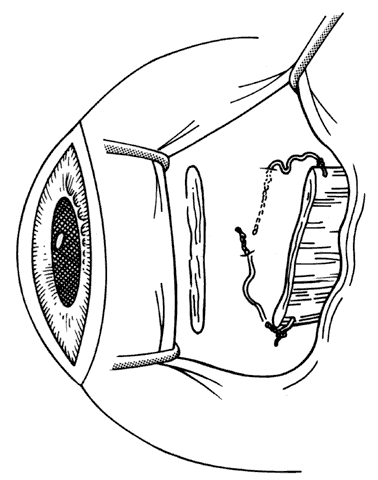

If a muscle has been lost, or has slipped from its original insertion, or when only the muscle capsule is attached to the globe and the actual muscle tissue has slid back through the muscle sleeve, the force generated by the muscle will be greatly diminished. Effort must be directed to finding and recovering the muscle tissue and reattaching it to the globe, thus restoring the contractile force of the muscle. Once disinserted, the most difficult muscle to find is the medial rectus muscle. This is because once the intermuscular membranes are cut, it has no attachments to other muscles and it can retract into the orbit. The other rectus muscles have attachments to other muscles that facilitate recovery. The superior rectus is attached to the superior oblique, the inferior rectus is attached to the inferior oblique, and the lateral rectus has attachments between the undersurface of the lateral rectus and the orbital surface of the inferior oblique. Once these attachments are identified, the small operculum in Tenon's capsule, through which the muscle sleeve passes, can usually be identified. When this operculum has been found, a forceps is used to grasp muscle tissue. If the patient has not been given atropine, bradycardia may occur when traction is applied to muscle tissue. It is important to avoid pulling Tenon's fascia forward in a blind attempt to find the muscle. This may cause the muscle to further retract from the opening in Tenon's capsule. It is preferable to gently displace the globe away from the area of surgical exploration with blunt retraction; vigorous rotation of the globe may cause further posterior slippage of the lost muscle. Once the muscle has been identified, it is helpful to place a locking Castroviejo forcep on the muscle or its tendon. This will reduce the chance that the recovered muscle will inadvertently slip out of the instrument and retract into the orbit. A hand-over-hand technique can be used to bring the remainder of the muscle tissue anterior. Once the muscle is brought anterior, a Jameson resection clamp can be applied to the muscle tendon. When a suture has been placed through the muscle, the clamp is removed (Fig. 41). The muscle can then be reattached to the globe in a position that, in the surgeon's best judgment, will provide the best alignment.

Fig. 41. When a muscle slips out of a clamp, becomes disinserted from its tendon, or is “lost,” it can be found by searching along the scleral surface to find an operculum in Tenon's capsule. Once muscle tissue is identified, it is brought handover-hand through the operculum and placed on a secure clamp such as a Jameson resection clamp.